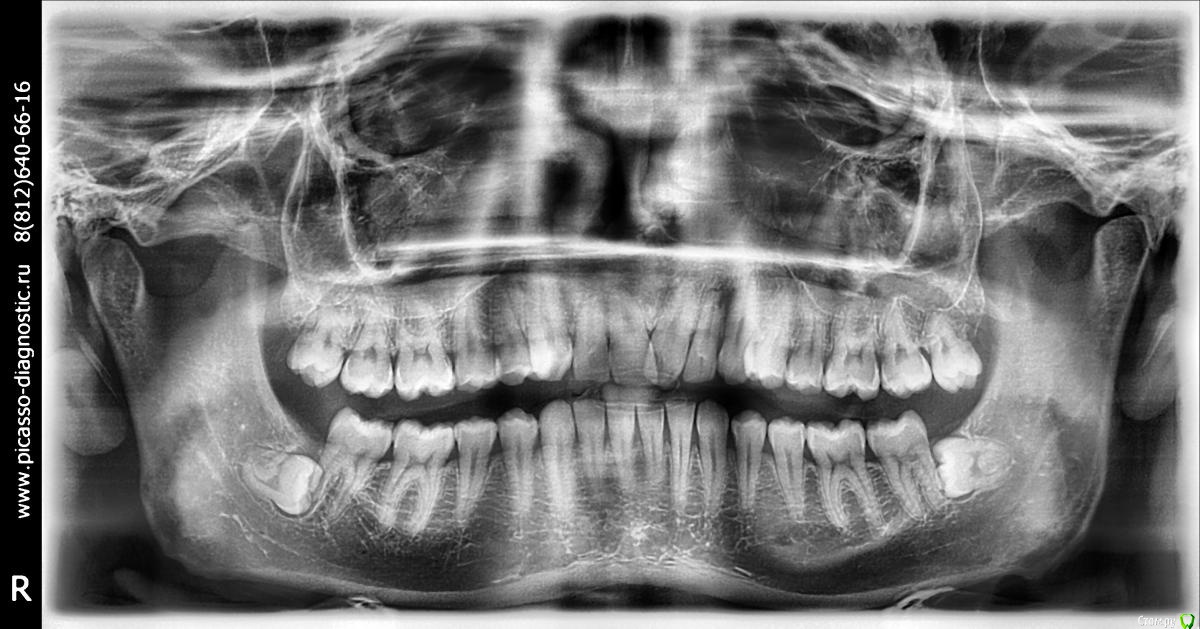

Мне 28 лет. У меня нет ни одной пломбы. Всю жизнь я хожу к стоматологом только на гигиеническую чистку. Последние несколько лет мне уже несколько врачей рекомендовали удалить четвёрки и поставить брекеты для исправления дистального прикуса. Один из ортодонтов также предлагал ЧЛХ нижней челюсти. Основной аргумент у врачей, что если не снизить нагрузку на дёсны от неправильного прикуса, то уже лет через 5 зубы начнут выпадать. Как видно на фото, дёсны уже значительно сползли, появился клиновидный дефект. С эстетической точки зрения меня всё устраивает. Хочу услышать ещё несколько мнений, как бороться с опусканием дёсен и стоит-ли заниматься исправлением прикуса.